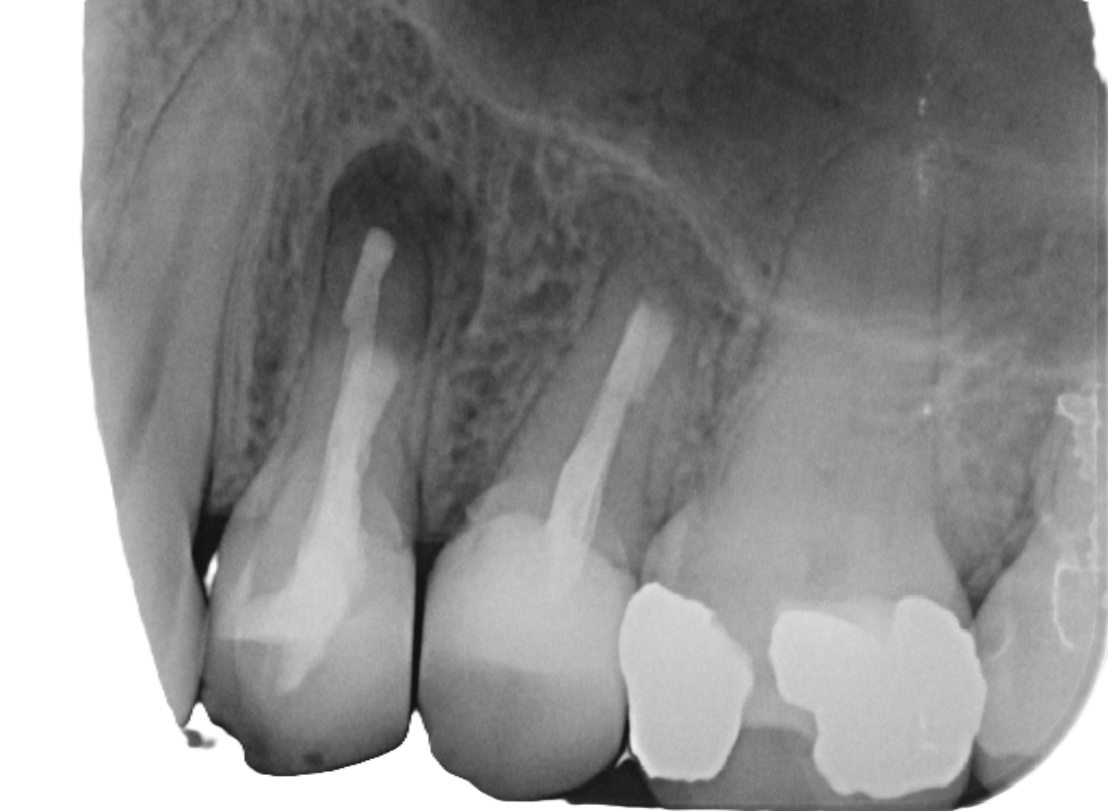

Zwei digitale Röntgenaufnahmen von Backenzähnen auf einem Monitor. Die Bilder zeigen Zahnwurzeln, Wurzelkanäle und den umgebenden Kieferknochen zur Beurteilung des Zahnzustands.

Vorher

Nachher